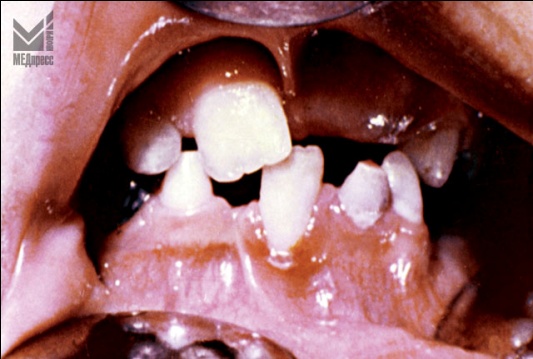

| Рис. 1. и 2. Гиперемия, отек десневого края в области фронтальных зубов. Шейки зубов оголены. Имеются пародонтальные карманы с грануляциями и гноетечением, отсутствие зубов. Дизокклюзия. Аномалийное положение зубов. |